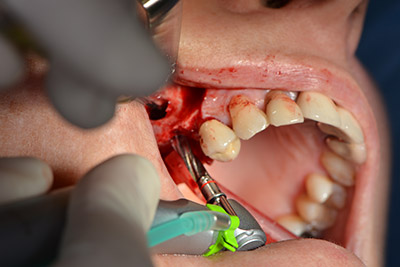

Im nächsten Schritt wird die Sinusbodenelevation mit simultaner Implantation durchgeführt. Für die bukkale Fensterung der Kieferhöhlenwand gibt es auch hier bei der Implantmed an der ersten Position eine Voreinstellung.

Mit 35.000/min wird das Fenster angelegt und anschließend die Schneidersche Membran nach kranial präpariert. (Abb. 13 bis 14).

Danach wird das Implantat eingebracht und der Knochen aufgebaut. Aufgrund der Größe des Augmentates wurde im vorliegenden Fall Eigenknochen, der als Bohrspäne bei der Implantation 16 und der Fenestration 14 angefallen ist und mit einer Knochenfalle aufgefangen wurde, mit Knochenersatzmaterial vermischt.